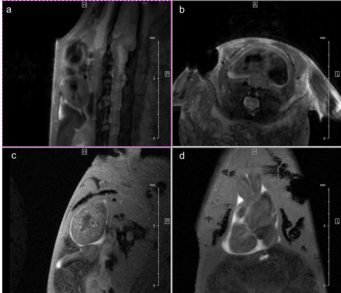

Fig. 2: Mouse heart MRI. In the upper panel the endsystolic (a) and enddiastolic (b) phase of a mouse heart in the 4-chamber-view is displayed. In red: position of the 7 slices, orthogonal to the septum (1.0 mm thick, no gap). In the lower panel in (c) the endsystolic and in (d) the enddiastolic phase of an axial midventricular slice is shown. Note the papillary muscle.